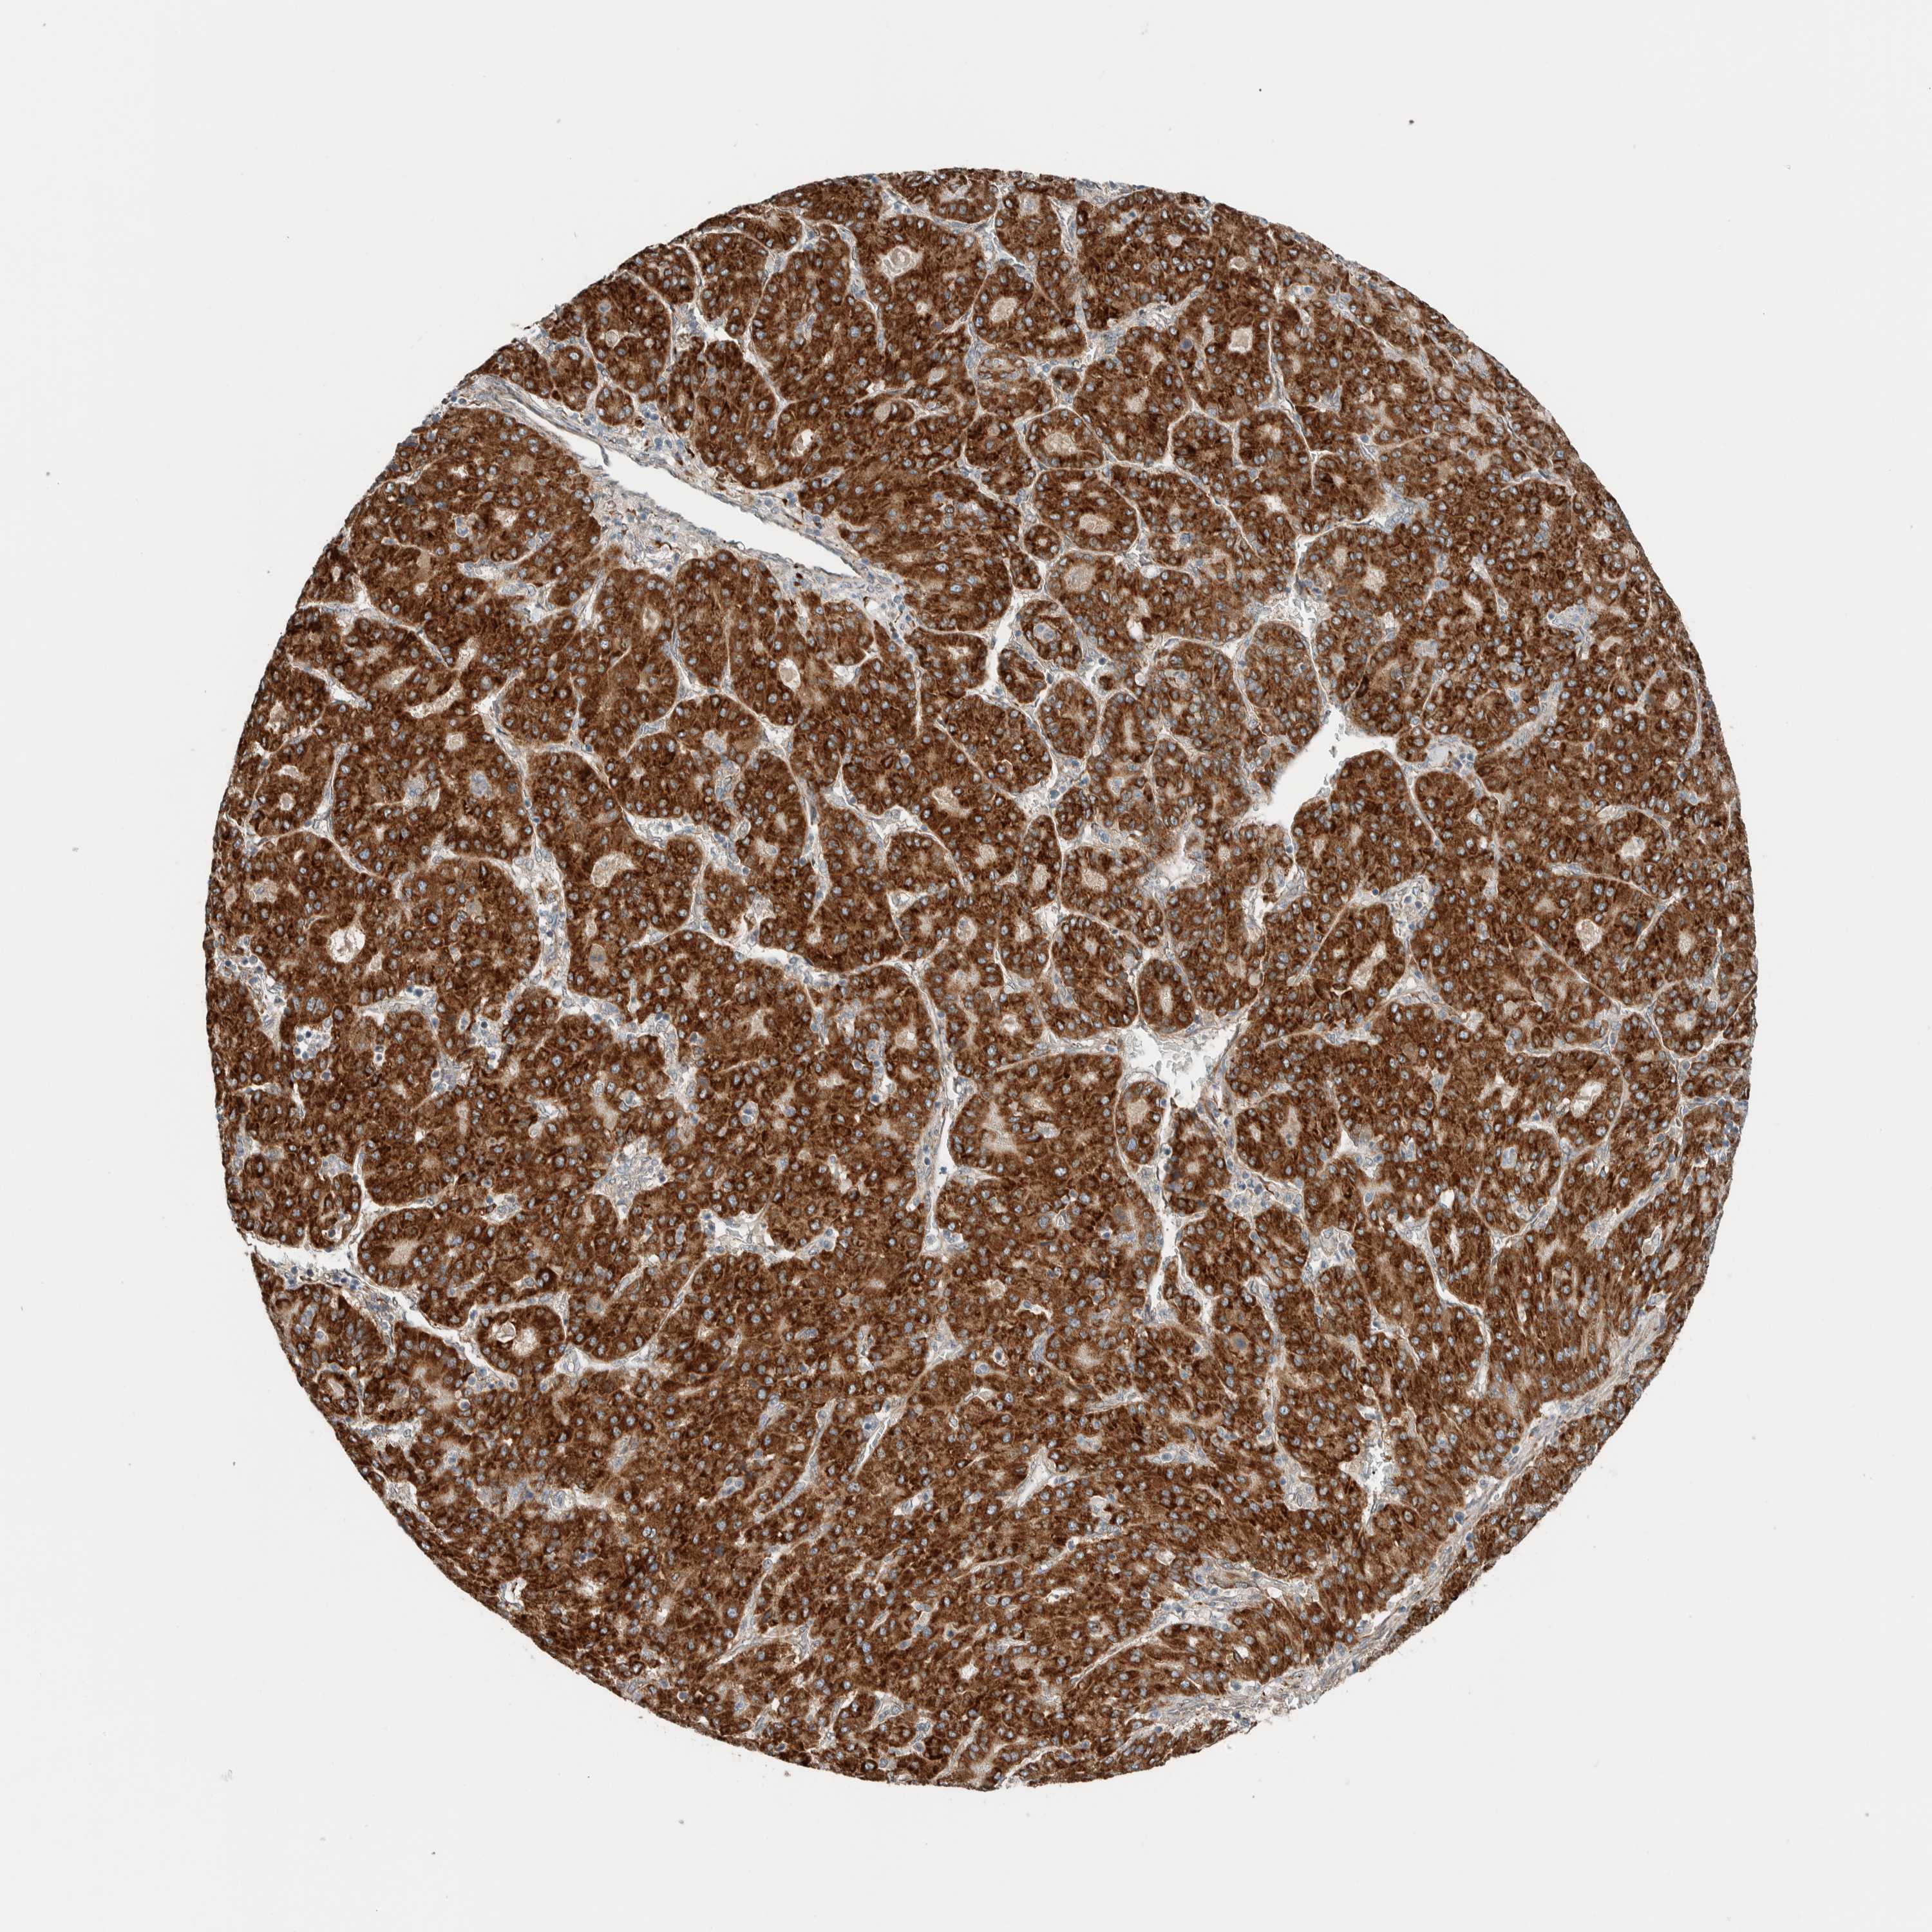

LIVER CANCER - Protein expressioni

A mouse-over function shows sample information and annotation data. Click on an image to view it in a full screen mode. Samples can be filtered based on level of antibody staining by selecting one or several of the following categories: high, medium, low and not detected. The assay and annotation is described here.

Note that samples used for immunohistochemistry by the Human Protein Atlas do not correspond to samples in the TCGA dataset.

Antibody stainingi

Antibody staining in the annotated cell types in the current human tissue is reported as not detected, low, medium, or high, based on conventional immunohistochemistry profiling in selected tissues. This score is based on the combination of the staining intensity and fraction of stained cells.

Each image is clickable and will lead to virtual microscopy that enables deeper exploration of all samples and also displays staining intensity scores, fraction scores and subcellular localization as well as patient and tissue information for each sample.

Antibody HPA023559

Antibody HPA023564

Antibody HPA044971

Antibody CAB031916

Staining

High

Medium

Low

Not detected

Intensity

Strong

Moderate

Weak

Negative

Quantity

>75%

75%-25%

<25%

None

Location

Nuclear

Cytoplasmic/membranous

Cytoplasmic/membranous,nuclear

Cholangiocarcinoma

Carcinoma, Hepatocellular, NOS